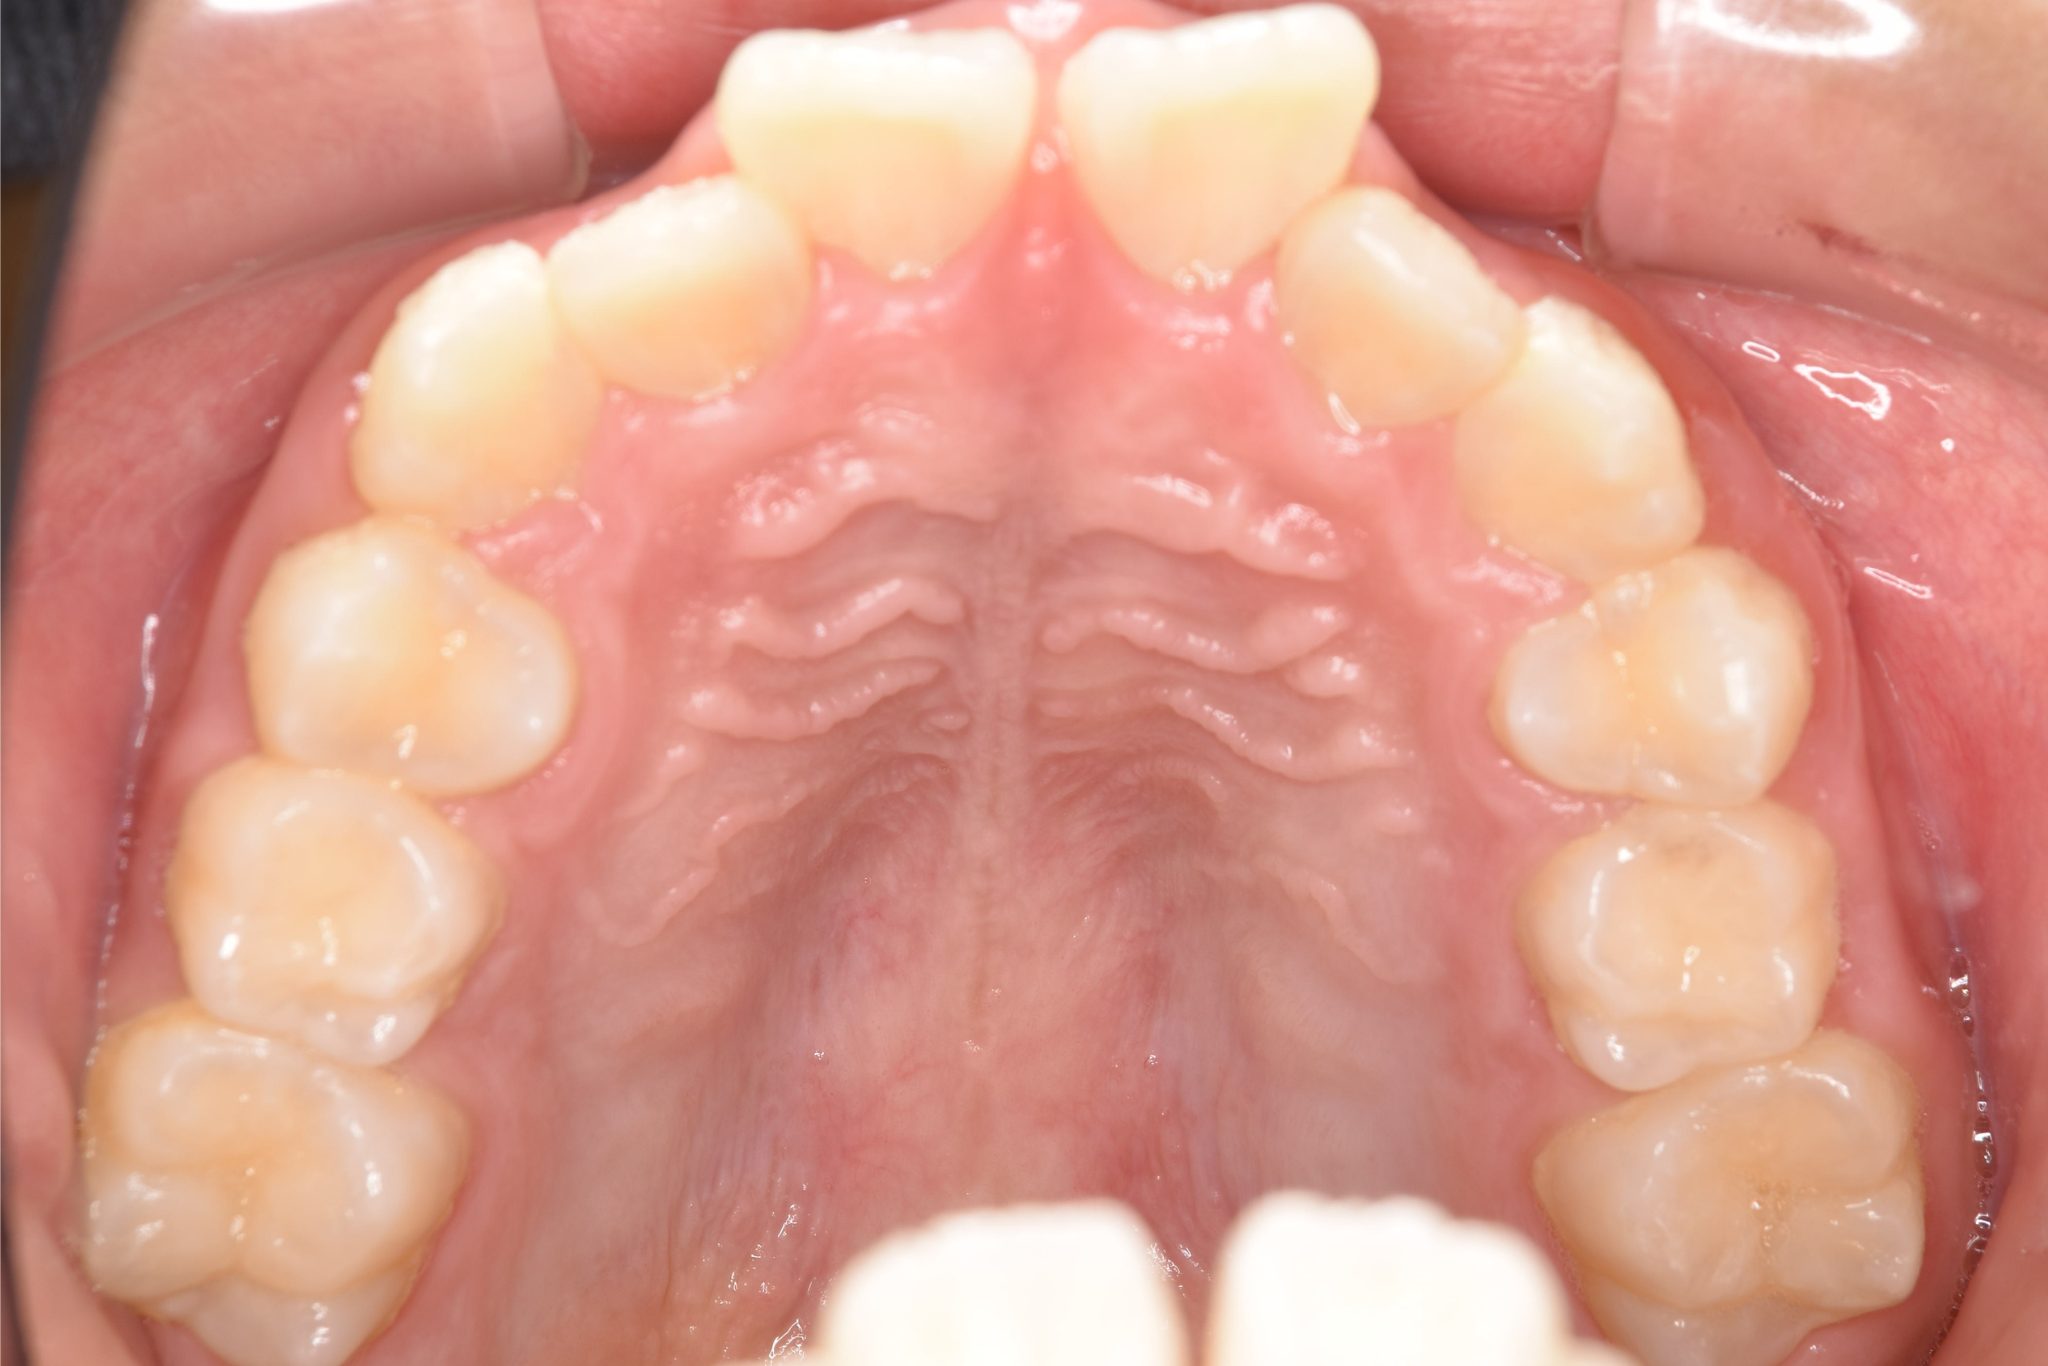

アフター

全顎ワイヤー矯正 症例_218

主訴 出っ歯|歯の隙間

施術内容 小児矯正1期治療

治癒期間 1年11ヶ月間

費用 465,400円(税込)